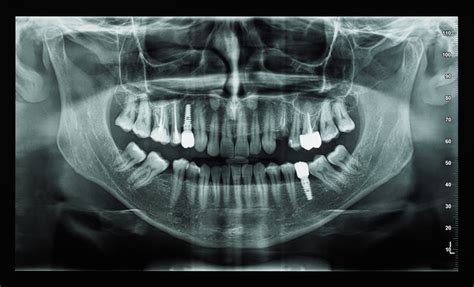

La radiografía panorámica dental, también conocida como ortopantomografía, es una herramienta fundamental en odontología que ofrece una vista completa de las estructuras dentales y maxilofaciales. Esta técnica radiológica es esencial para el diagnóstico y la planificación de tratamientos, ya que permite identificar problemas bucodentales que no son perceptibles a simple vista.

La ortopantomografía es un estudio radiológico que permite observar todos los dientes, tejidos de soporte y estructuras anatómicas adyacentes. Se trata de una imagen bidimensional de un objeto tridimensional, por lo que las imágenes pueden superponerse. Aunque es una radiografía muy útil para un diagnóstico inicial, esta superposición algunas veces impide una visualización detallada de ciertas patologías.

En una radiografía panorámica se pueden ver una infinidad de estructuras anatómicas. Para empezar, podemos ver tanto los dientes superiores como los inferiores y sus respectivas raíces. A continuación podemos ver el hueso, clave en la colocación de implantes.

A partir de aquí en la ortopantomografia se pueden ver una infinidad de estructuras anatómicas. Entre ellas encontramos:

Una de las principales ventajas de la radiografía panorámica dental es que proporciona una imagen completa de las estructuras anatómicas de la cavidad bucal y sus alrededores. Esta vista general facilita a los profesionales de la odontología evaluar y diagnosticar diversas afecciones con mayor precisión. Gracias a su capacidad para mostrar todas las estructuras anatómicas de manera integral, la radiografía panorámica dental se ha convertido en una herramienta imprescindible para evaluar la salud bucodental de los pacientes.

Visión general de la boca y los dientes. Las radiografías panorámicas proporcionan una vista completa de los dientes, las encías, los huesos y los tejidos blandos de la boca. Permiten al dentista obtener una imagen precisa de las piezas dentales y los huesos de la mandíbula. Una radiografía panorámica puede realizarse en unos pocos minutos y no requiere la toma de múltiples imágenes para obtener una visión completa de la boca y los dientes.

En una radiografía panorámica se pueden ver todas las piezas dentales, incluyendo aquellas que aún no han erupcionado completamente.

Gracias a su capacidad para identificar una amplia gama de problemas dentales y maxilofaciales, las radiografías panorámicas son un pilar en la planificación y diagnóstico odontológico. En conjunto, una radiografía panorámica ofrece una visión detallada que permite diagnosticar diversas condiciones dentales, desde caries hasta problemas de las encías y anomalías en la posición de los dientes.